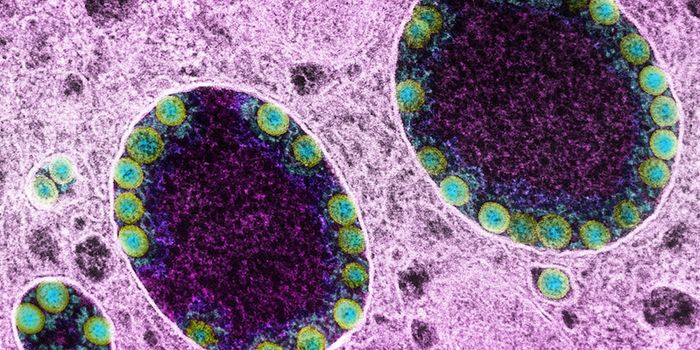

APR 04, 2022Cell & Molecular BiologyAbout 1.5 million new HIV infections are thought to have occurred last year, and while COVID-19 has dominated concerns a ...